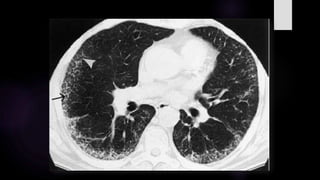

Diversos estudios han podido establecer algunos hallazgos frecuentes en las TEM de los

pacientes con COVID19:

1. Opacidad en vidrio esmerilado de localización periférica o subpleural, uni o bilateral:

ha sido reportada en varias series con porcentajes que van desde 56% al 96% de los casos.

2. Consolidaciones entre el 50% al 62%.

3. Engrosamiento del septo interlobular con rangos del 35% al 59%.

4. Consolidaciones más opacidad en vidrio esmerilado hasta en el 50% de los

casos.